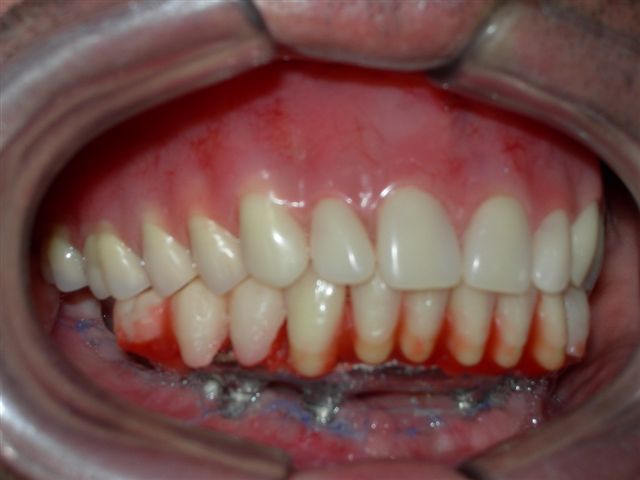

| Próteses antagonistas (VISTA DIREITA) |

Próteses antagonistas (VISTA ESQUERDA) |